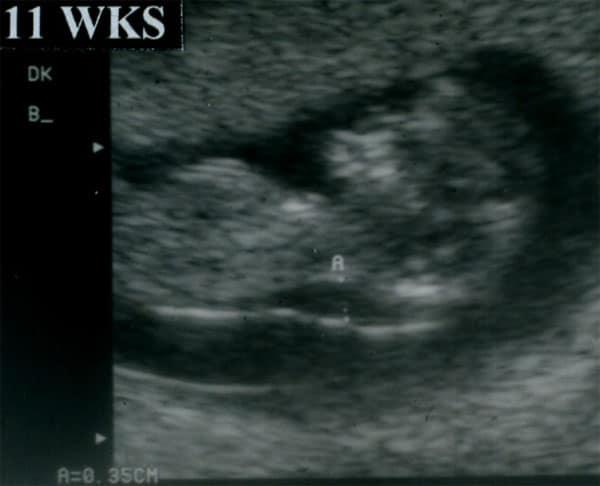

Learn how to effectively use ultrasound to detect trisomy 13, a rare chromosomal condition with significant fetal anomalies. This course covers key sonographic findings in both the first and second trimesters, including nuchal translucency, facial clefts, holoprosencephaly, and cardiac anomalies. Gain insights into the distinct facial and central nervous system abnormalities commonly associated with trisomy 13, and learn how to identify soft markers like shortened limbs and echogenic bowel. Detailed protocols for anatomic surveys and dynamic scanning techniques will help you improve detection rates and accurately identify trisomy 13 in high-risk pregnancies. Understand how maternal age and gestational age affect trisomy 13 risk and learn the importance of combining ultrasound findings with genetic testing.

Identify major defects on the sonogram associated with Trisomy 13.